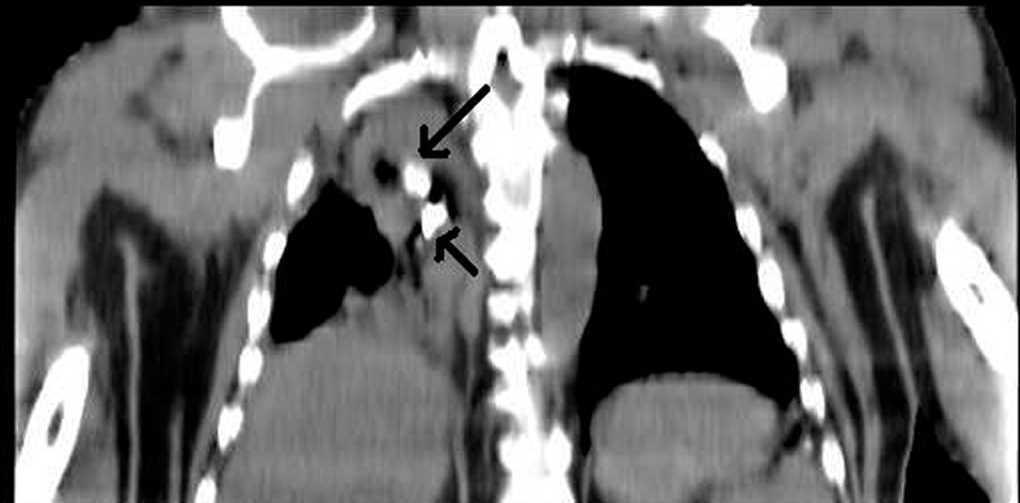

Paciente de 45 años de edad, sin antecedentes médicos de interés, que es remitido a la Unidad de Cuidados Intensivos tras sufrir accidente de tráfico. En la exploración física se aprecia hipoventilación en hemitórax derecho. Ingresa intubado y conectado a ventilación mecánica. Se realiza radiografía de tórax donde se evidencia una atelectasia del hemitórax derecho en el contexto de un traumatismo torácico con existencia de dos cuerpos extraños de densidad radioopaca (fig. 1). Debido a persistencia de alteraciones en la gasometría pese a ventiloterapia, se realizó tomografía computarizada (TC) pulmonar urgente hallándose dos piezas dentarias a nivel endobronquial (fig. 2, reconstrucción coronal). Posteriormente se procedió a extracción de las mismas mediante broncoscopia. Se trataba de una atelectasia postraumática por impactación de dos piezas dentarias a nivel endobronquial.

Figura 2